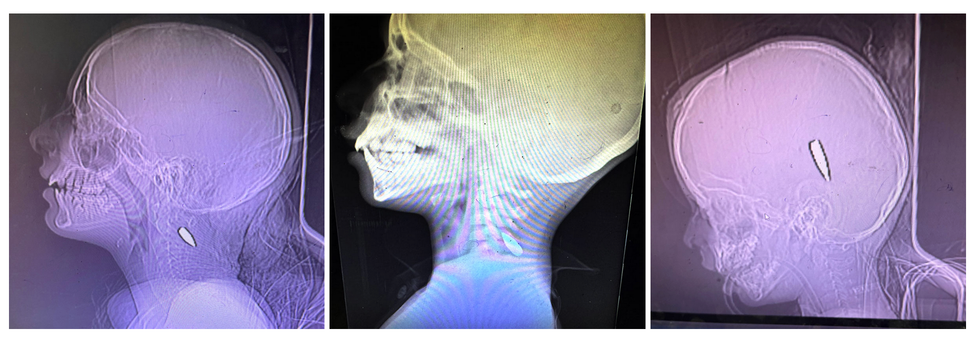

The essay, bylined by trauma surgeon Feroze Sidhwa, includes three photos of X-rays that Mimi Syed—an emergency medicine doctor based in Olympia, Washington—provided to the Times.

"I had multiple pediatric patients, mostly under the age of 12, who were shot in the head or the left side of the chest," Syed, who worked in Khan Younis from August 8 to September 5, told the newspaper. "Usually, these were single shots. The patients came in either dead or critical, and died shortly after arriving."